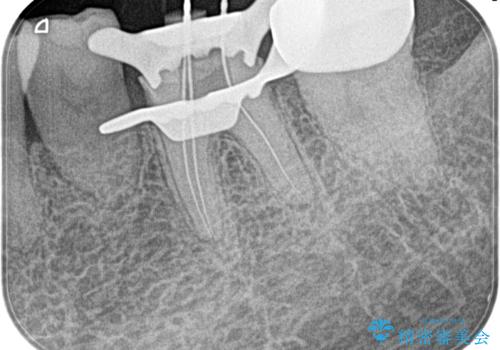

奥歯がズキズキ痛い 根管治療

- 冷たいもので強い痛みがあり、1週間前ぐらいからズキズキ痛いことを主訴に来院されました。

患歯に冷温刺激に対し20秒の持続痛と打診を認めたため、不可逆性歯髄炎の診断とし治療を行なっております。

- 精密根管治療(イニシャルケース,大臼歯):122,000円、ファイバーコア:22,000円費用は治療当時の料金となります

不可逆性歯髄炎と診断される場合は、経過観察を行なっても正常歯髄に戻る可能性は極めて低いため今回の処置のように抜髄の適応となります。